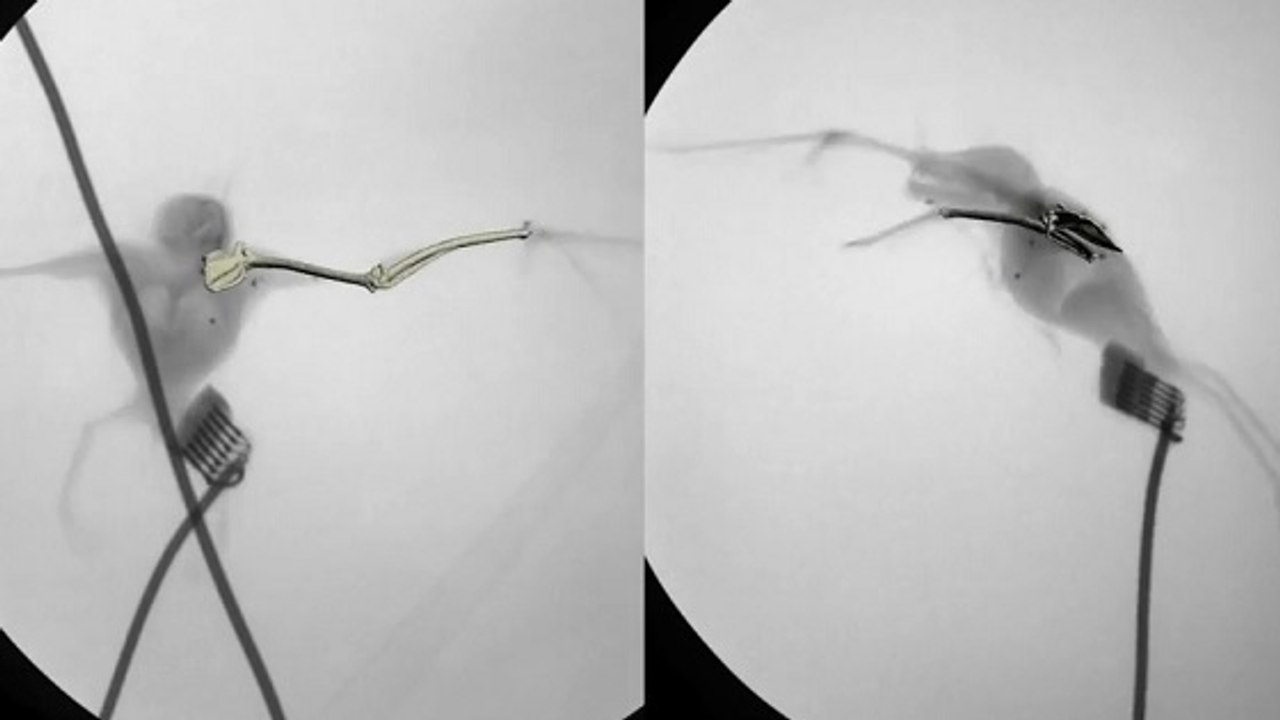

Des chercheurs de l'institut MIT et de l'université Harvard ont conçu des muscles artificiels et légers inspirés des pliages de l’origami japonais. Dotés de ces muscles, des robots soulèveront jusqu’à mille fois leur poids.